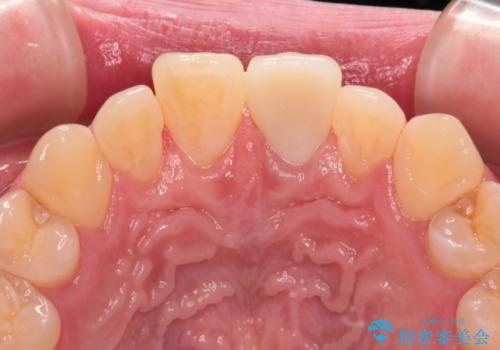

- 転んだ際に欠けてしまった前歯の変色が気になるとのことで来院された患者様です。

診察やレントゲン写真より神経組織の失活が認められたため、根管治療、ファイバーコアによる土台築製後、オールセラミッククラウンにて補綴することとしました。